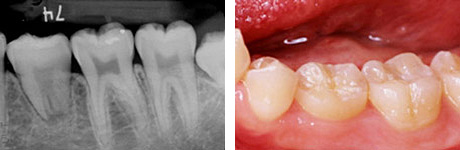

歯根完成歯親知らずの移植

左:治療前のCT画像。

右:治療前の口腔内。

24歳、女性。右下第二大臼歯部(受容側)へ親知らず(ドナー歯)を移植してほしいという希望で来院されました。

ドナー歯はすでに歯根が完成しています。このような場合、移植後に歯髄(神経)の治療が必要です。

左:移植のために抜歯された親知らず(ドナー歯)。

右:移植直後。

左:移植直後のエックス線写真。

右:移植後1ヶ月。

根管治療直後。歯根が完成している歯を移植歯として用いた場合、歯の神経はつながらないので、このように神経の治療が必要になります。

移植後4ヶ月。

移植歯はコンポジットレジンで修復が行われています。